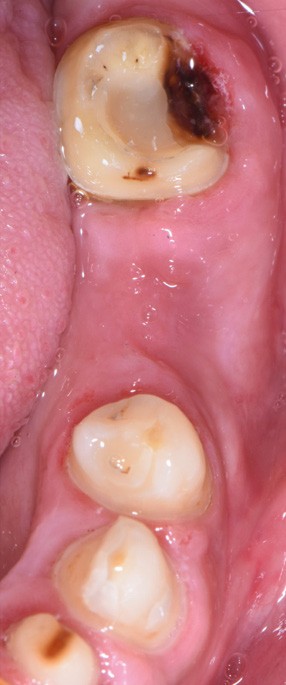

Au vu du contexte para-fonctionnel et de l’étendue de la perte tissulaire, des coiffes périphériques minimalement invasives ont été choisies afin de restaurer l’esthétique et la fonction. Actuellement, aucun consensus n’est fait sur le choix du matériau d’infrastructure à privilégier. Les matériaux hybrides usinables présentent des propriétés mécaniques, physiques et biologiques intéressantes en contexte d’usure sévère (e.g., module d’élasticité, résistance à la propagation de fêlures, facilité de réintervention). Une réhabilitation globale avec remontée de dimension verticale d’occlusion (DVO) par l’intermédiaire de coiffes composites renforcés en nano-céramiques est décrite.